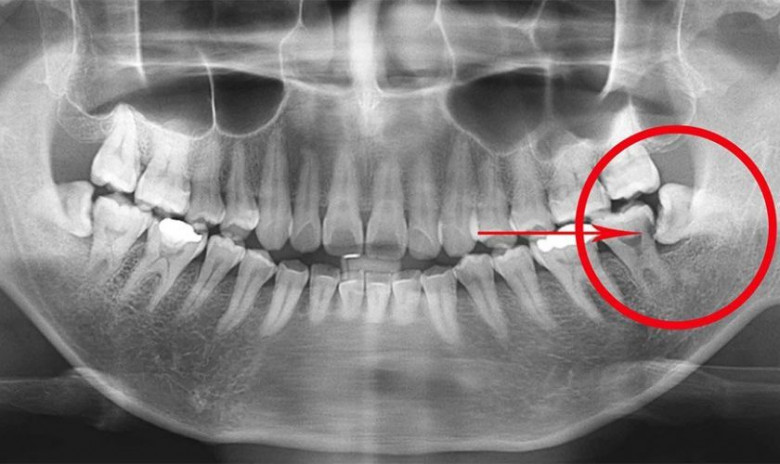

Ատամնաբույժների մեծ մասը խորհուրդ է տալիս հեռացնել իմաստության ատամնրը՝ դա հիմնավորելով, որ այդ ատամները պետք չեն:

Բժիշկ Ջեյ Ֆրիդմանի պնդմամբ՝ իմաստության ատամների երկու երրրոդը հեռացման կարիք չունի, հիվանդները կարգին վիճակում կլինեն, եթե պահպանեն այդ ատամները:

Իմաստության ատամների հեռացումը հղի է առողջության համար լուրջ ռիսկերով: Փաստ է, որ շատերը մշտական ծակոց կամ տհաճ զգացողություն են ունենում իմաստության ատամները հանելուց հետո, նշանակում է, որ ատամներն իսկապես կապված են մարմնի տարբեր մասերի հետ: